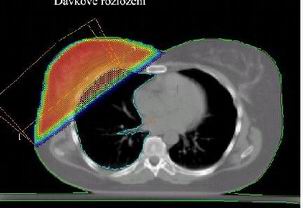

Dvě tangenciální hrudní pole

většinou s klíny

Společné izocentrum pro všechna pole